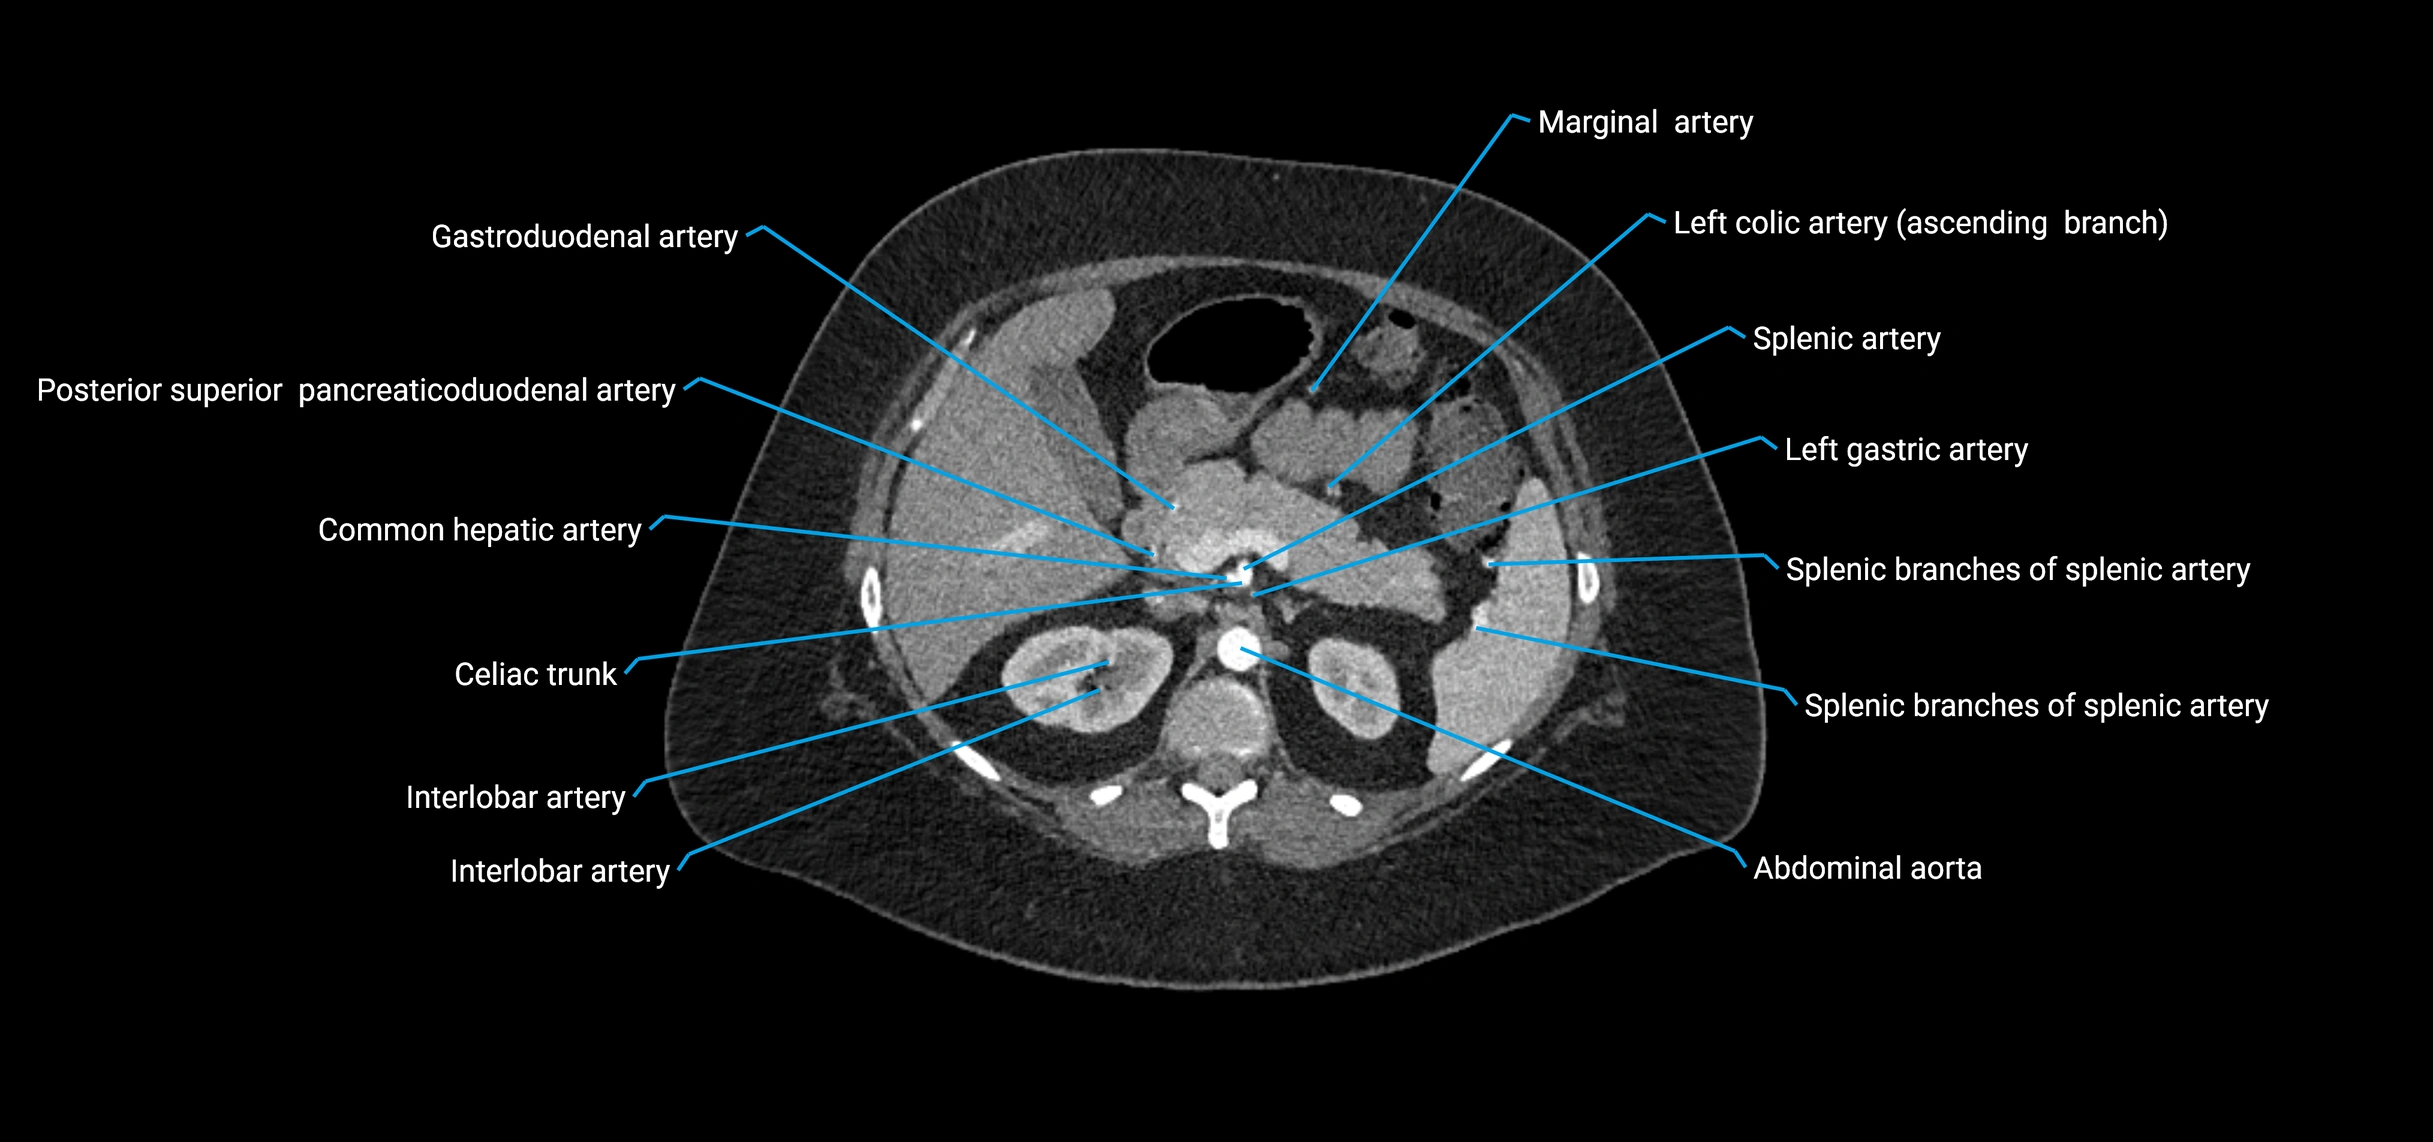

• Unpaired visceral branches: celiac trunk, superior mesenteric artery (SMA), inferior mesenteric artery (IMA)

Contrast-enhanced CT (CTA):

• Gold standard for abdominal aortic imaging

• Provides excellent detail of lumen, wall, aneurysm, thrombus, and branch vessels

• Multiplanar and 3D reconstructions help in aneurysm measurement, stent graft planning, and dissection evaluation

• Detects acute rupture, traumatic injury, or occlusion with high sensitivity